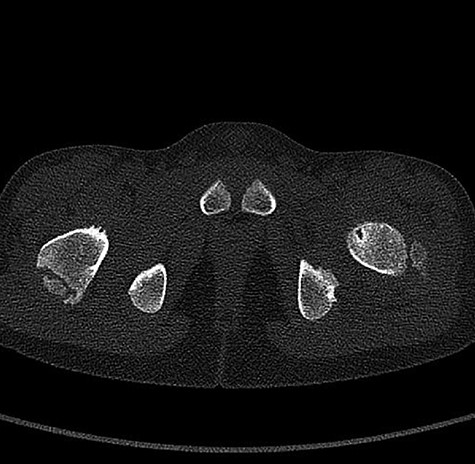

CT hips reported a well-defined lesion seen bilaterally in the neck of femur anterior infero-medial aspect, more prominent on the left side measuring 7 x 3 mm on left side both in coronal (Fig. 3) and axial (Fig. 4) views. On the right side, other lesion measuring 2 x 1 mm (Fig. 5) seen in coronal view. These two lesions are well defined with a sclerotic border with a small cortical defect. The lesion shows fat density. The symmetrical appearance of the lesion combined with the fat density and location suggest the diagnosis of synovial herniation pit. MRI Pelvis revealed minimal left hip joint effusion with loculated fluid seen along the trochanteric bursa with the largest measuring 0.9 x 1.5 cm (Fig. 6, 7).

Showed coronal cut of CT hips demonstrating the synovial pit prominent right side.